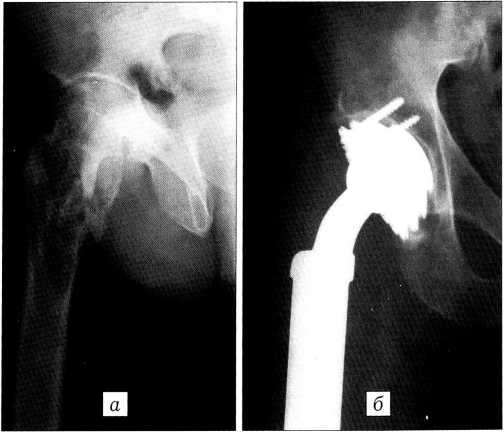

Больной С-н,42 лет, рабочий-нарезчик металла. Поступил в больницу № 62 после обследования в ЦИТО и Институте онкологии им. П.А. Герцена с диагнозом «хондросаркома проксимального отдела правой бедренной кости». Клинически в области большого вертела и несколько кзади от него определяется плотное неподвижное по отношению к кости опухолевидное образование 6x4 см. На рентгенограммах: верхний метаэпифиз бедренной кости занят очагом деструкции, на фоне которой видны плотные включения кальция; выраженная периостальная реакция, мягкотканный компонент в области большого вертела (рис. 3). Заключение: хондросаркома.

Рис. 3. Рентгенограммы больного С-на до (а) и после (б) операции.

Больному произведена операция — резекция проксимального суставного конца бедренной кости длиной 18 см. При обнажении области патологического очага выявлено костной плотности опухолевидное образование, и сомнений в том, что это опухоль, не было. В мягких тканях ягодицы имелись два небольших плотных опухолевидных узла, которые были иссечены со слоем окружающих мышц. На уровне пересечения бедренной кости подозрительным казалось содержимое костномозгового канала, в связи с чем кость дополнительно резецирована на протяжении 2 см. После удаления проксимального суставного конца бедренной кости обнаружено, что суставной хрящ вертлужной впадины частично разволокнен. Произведено удаление его овальным долотом. Пострезекционный дефект замещен эндопротезом Сиваша.

Данные гистологического исследования операционного препарата: очаг деструкции бедренной кости и отдельные узлы мягких тканей окружены плотной фиброзной капсулой, изнутри выстланной хитиновой оболочкой, с типичным для эхинококкоза содержимым и участками отложения кальция; в дополнительно удаленном участке кости — выраженный фиброз. Заключение: эхинококкоз кости.

Больной Ч.,65 лет, по поводу небольших болей в области тазобедренного сустава консультирован в поликлинике одного из клинических учреждений Москвы, которое занимается костной онкологией. На основании осмотра больного и просмотра рентгенограмм был поставлен диагноз «фиброзная дисплазия проксимального отдела бедренной кости», что зафиксировано в выданной больному справке. Известно, что фиброзная дисплазия — одна из наиболее доброкачественных форм костной патологии. Биопсия с целью морфологической верификации диагноза не проводилась. Врача-консультанта могло бы насторожить то, что больному 65 лет, а фиброзная дисплазия в этом возрасте выявляется весьма редко. Через несколько месяцев у больного произошел патологический перелом. Он был госпитализирован в травматологическое отделение и после наложения гипсовой повязки выписан домой. Вероятно, над травматологом довлело заключение специалистов по костной патологии. В течение 5 мес больной лечился на дому. После снятия гипсовой повязки обнаружилась значительных размеров припухлость, и больной был госпитализирован в больницу № 62.

Клинически выявляется больших размеров плотная неподвижная опухоль проксимального отдела бедренной кости, а на рентгенограммах — обширный очаг деструкции, весьма характерный для хондросаркомы. Диагноз подтвержден данными биопсии. Больному произведена экзартикуляция бедра. Если бы характер процесса был распознан вовремя, возможно, удалось бы ограничиться резекцией бедренной кости с эндопротезированием.